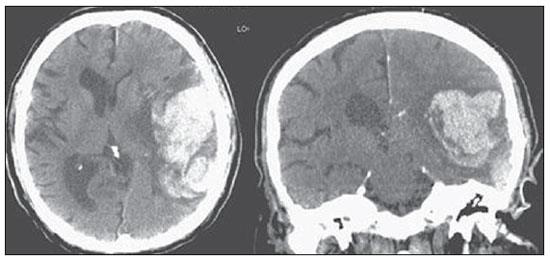

Analise a tomografia abaixo e indique qual o achado:

Hemorragia intraparenquimatosa.